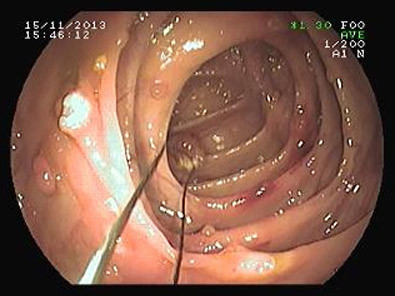

| Các khối u lành nằm rải rác trong ruột già và đang được cắt bỏ qua nội soi ruột già (ảnh chụp trực tiếp qua máy nội soi- BS Lưu Phương). |

Tại Phòng nội soi tiêu hóa, BV Nguyễn Tri Phương, với phương pháp nội soi ruột già từ đường hậu môn lên, chúng tôi đã tiến hành cắt thành công gần 40 (36 - 37) cái polyp (u lành) ở ruột già cho bệnh nhân mà không cần phẫu thuật.